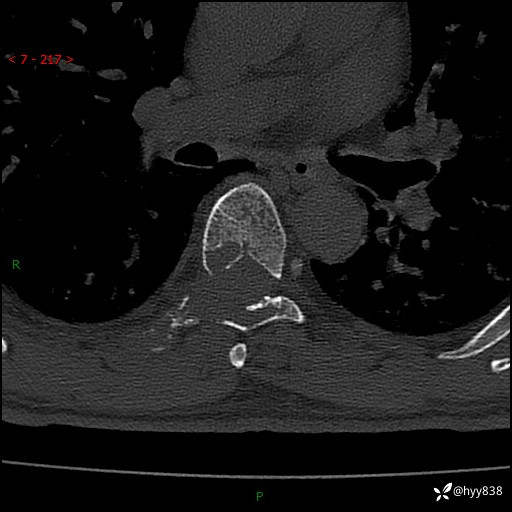

胸椎CT平扫(骨窗+软组织窗)